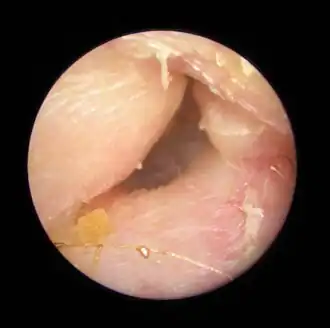

Exostoses dans le conduit auditif, vues par otoscopie.

Du fait de la réduction du diamètre du conduit auditif, l'eau et le cérumen peuvent rester piégés entre la masse osseuse et le tympan et provoquer ainsi une infection comme une otite externe, particulièrement douloureuse.

Le contact de l’os avec le tympan peut provoquer des acouphènes[4]. Si rien n'est fait, les excroissances osseuses peuvent conduire à une obturation du conduit auditif et à une perte d'audition[1].